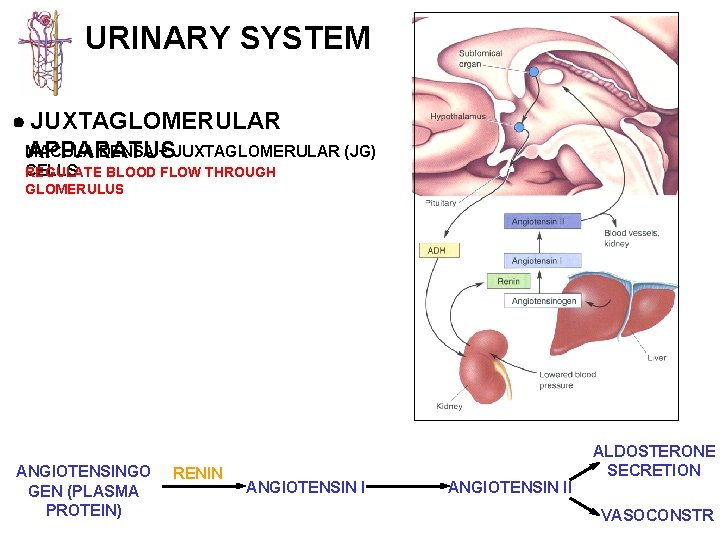

URINARY SYSTEM JUXTAGLOMERULAR MACULA DENSA + JUXTAGLOMERULAR (JG) APPARATUS CELLS REGULATE BLOOD FLOW THROUGH GLOMERULUS MACULA DENSA - cells located in the DCT in close contact with the glomerulus and the afferent and efferent arterioles JG CELLS - specialized smooth muscle cells in the wall of the afferent arteriole which contain and secrete RENIN to regulate blood flow through the glomerulus ANGIOTENSINGO GEN (PLASMA PROTEIN) RENIN ANGIOTENSIN II ALDOSTERONE SECRETION VASOCONSTR

URINARY SYSTEM JUXTAGLOMERULAR MACULA DENSA + JUXTAGLOMERULAR (JG) APPARATUS CELLS REGULATE BLOOD FLOW THROUGH GLOMERULUS BARORECEPTOR THEORY - assumes JG cells function as stretch receptors (high blood pressure would inhibit release of renin) MACULA DENSA THEORY - assumes the secretion of renin is regulated by the composition of the fluid in the DCT / afferent arteriole (low sodium would increase the release of renin) ANGIOTENSINGO GEN (PLASMA PROTEIN) RENIN ANGIOTENSIN II ALDOSTERONE SECRETION VASOCONSTR

URINARY SYSTEM JUXTAGLOMERULAR MACULA DENSA + JUXTAGLOMERULAR (JG) APPARATUS CELLS REGULATE BLOOD FLOW THROUGH GLOMERULUS ANGIOTENSINGO GEN (PLASMA PROTEIN) RENIN ANGIOTENSIN II ALDOSTERONE SECRETION VASOCONSTR